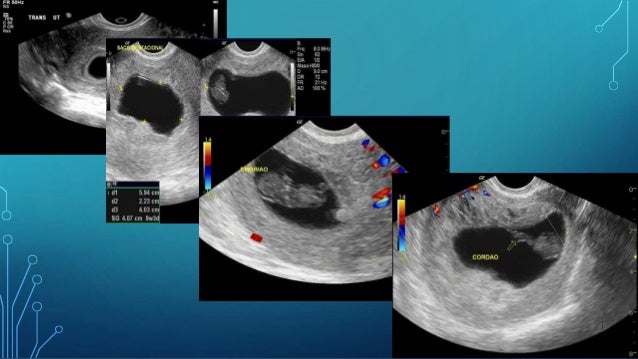

First Trimester Pregnancy Abnormalities Iconographic Essay

Abnormal First Trimester Scan